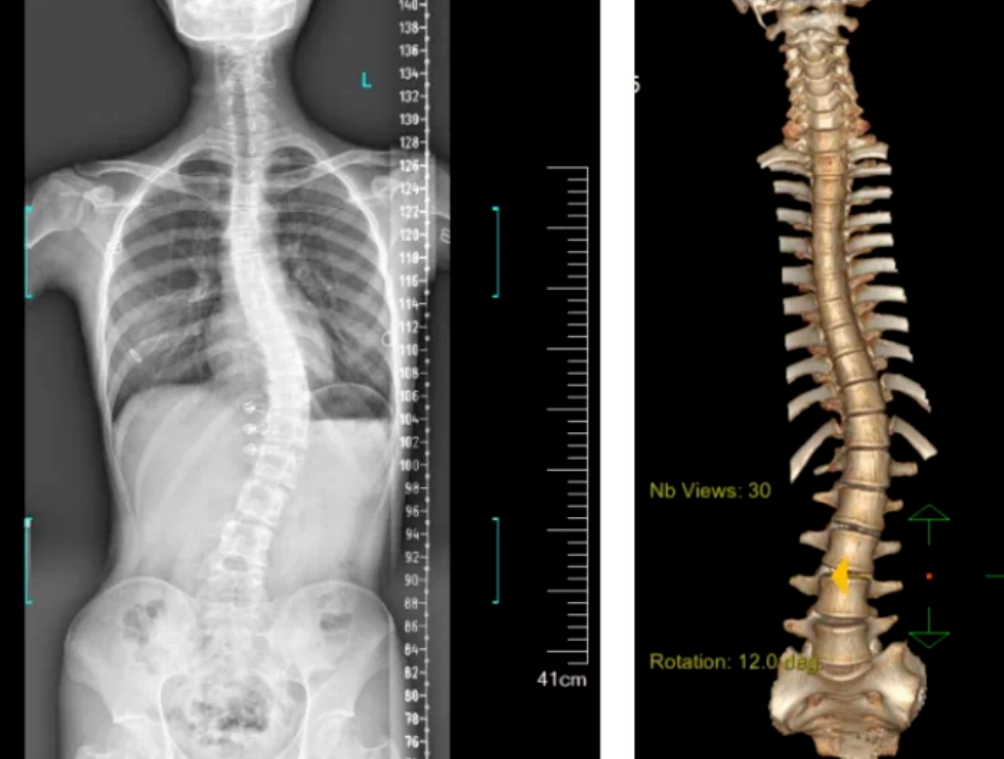

3D機器視覺的脊柱檢測圖

3D視覺技術可以用于自動化的脊柱側彎檢測。通過使用3D成像設備,如結構光或激光掃描儀,機器人可以快速捕捉老年人的脊柱圖像,并利用機器視覺算法分析脊柱的形態和角度,從而判斷是否存在側彎現象。

系統掃描速度為15Hz,精度達到±0.01mm,結合自研智能算法,能夠進行全彩信息學習,還能通過深度攝像頭捕捉人體背部的形態變化,轉化為對應的脊柱形態,并計算脊柱的彎曲角度,從而了解患者的側彎程度。這種方法避免了傳統X光片檢測帶來的輻射風險,實現了無輻射、快速、便捷的篩查。